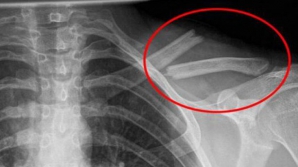

SEMNAL DE ALARMĂ: Tinerii dezvoltă oase asemănătoare unor coarne, din cauza utilizării telefonului mobil